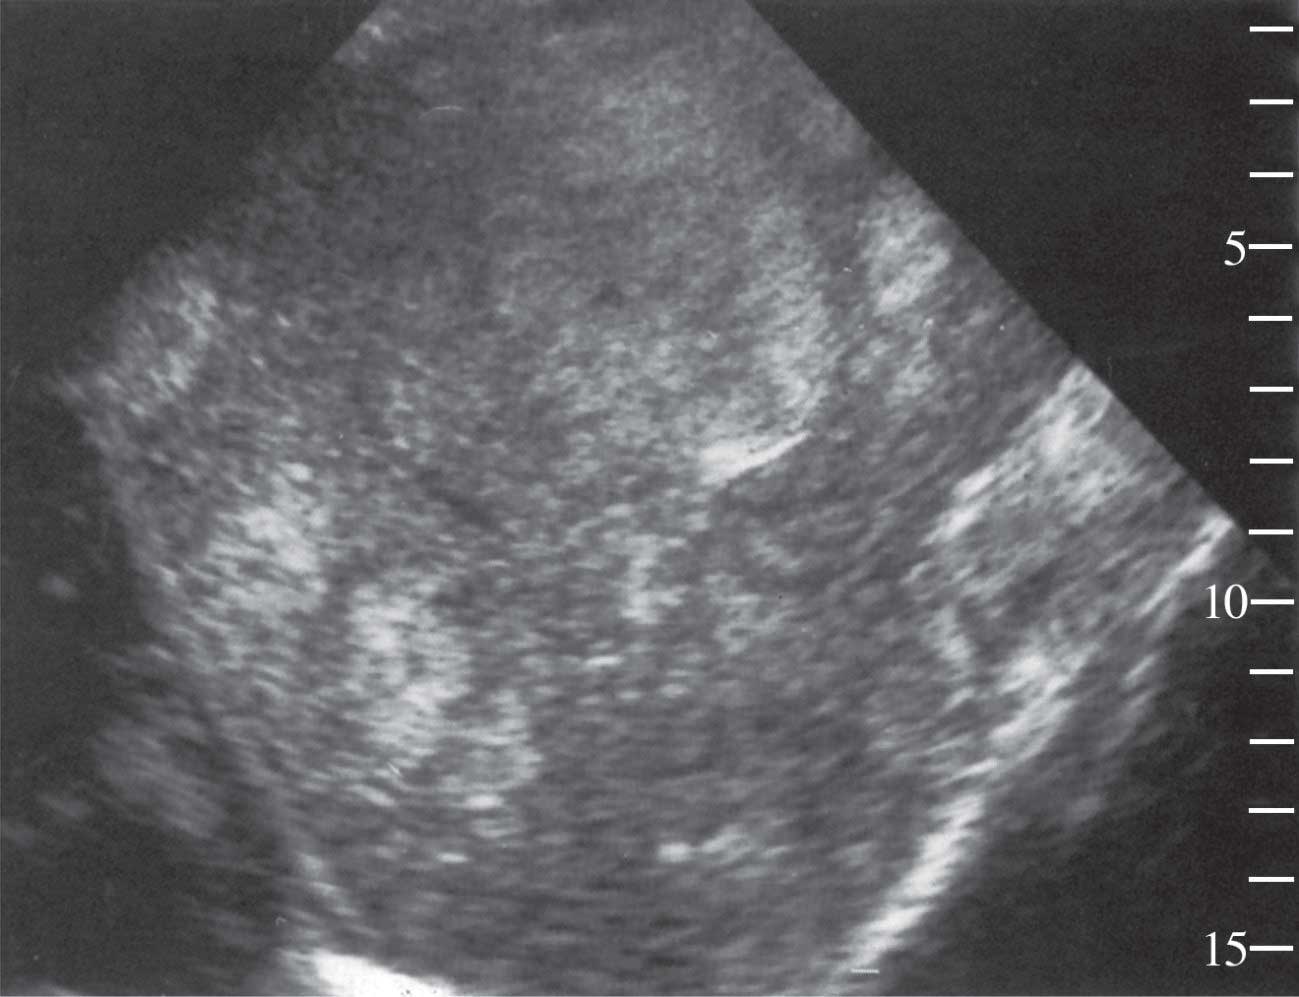

![]() |

| الشكل (1) سرطانة الخلية الكبدية كما تبدو بتخطيط الصدى (الأسهم) |

أ- تخطيط الصدى الذي يكشف عموماً وجود كتلة متفاوتة الحجم ضمن الكبد، ناقصة الصدى عادة ومتجانسة في أغلب الأحيان، بيد أنها قد تكون غير متجانسة (متغايرة) بسبب النخر أو النزف الذي يحدث فيها. أما باقي النسيج الكبدي فيبدو زائد الصدى وغير متجانس بسبب وجود التشمع المرافق. وكثيراً ما يكشف تخطيط الصدى اجتياح الورم لوريد الباب وفروعه الرئيسة أو الأوردة الكبدية، ويتضح ذلك بصورة أدق بعد الاستعانة بالدوبلر الملون. يستطيع التفرس بتخطيط الصدى كشف الأورام التي لا يقل قياسها عن 2سم، بيد أنه لا يمكن بهذه الطريقة التفريق بين السرطان وغيره من الكتل الكبدية الصلبة.